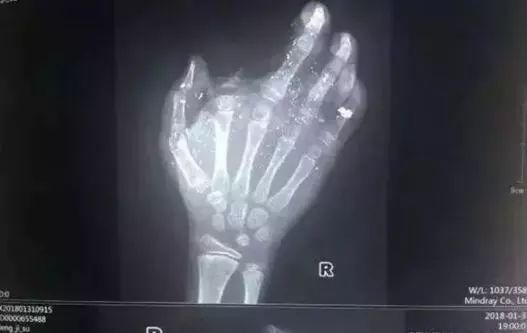

2018年1月,广西发生一起手机爆炸事件,一名年仅12岁的小男孩手掌被炸得血肉模糊,拇指、中指、无名指也都炸伤。